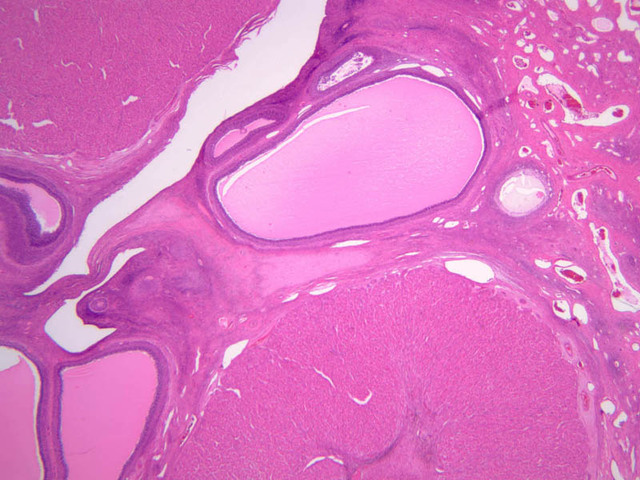

Corpus Luteum

After rupture of the Graafian follicle, the walls collapse and become folded. Thus, strands of tissue from the theca interna penetrate, to some extent, the mass of granulosa cells. Bleeding from the theca interna may form a blood clot in the antrum. The majority of the cells of the corpus luteum are derived from the granulosa cells. Both the granulosa cells and the cells of the theca interna enlarge and accumulate lipid, thus becoming lutein cells. There are two types of lutein cells - granulosa lutein cells that have a large, vesicular nucleus and vacuolate cytoplasm, and theca lutein cells that are distinguished by smaller darker nuclei. Corpus Luteum (slide B-54, human ovary, H&E [1x-labeled, 2.5x, 10x, 20x, 40x-labeled] [1x-labeled, 1x, 2.5x] [1x, 1x, 1x] 1x, 2.5x, 10x]; B-95, H&E [2.5x])